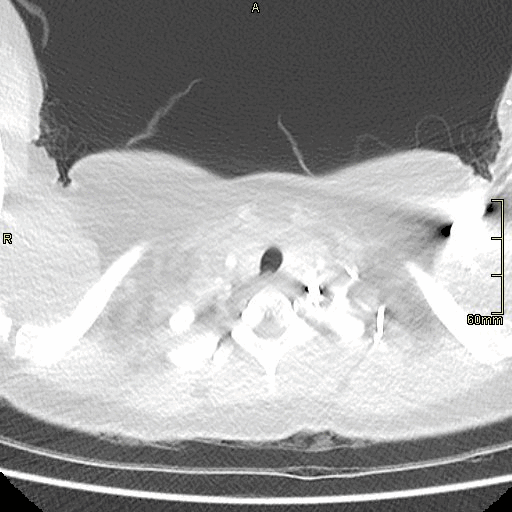

Lung (Axial)

Lung (Coronal)